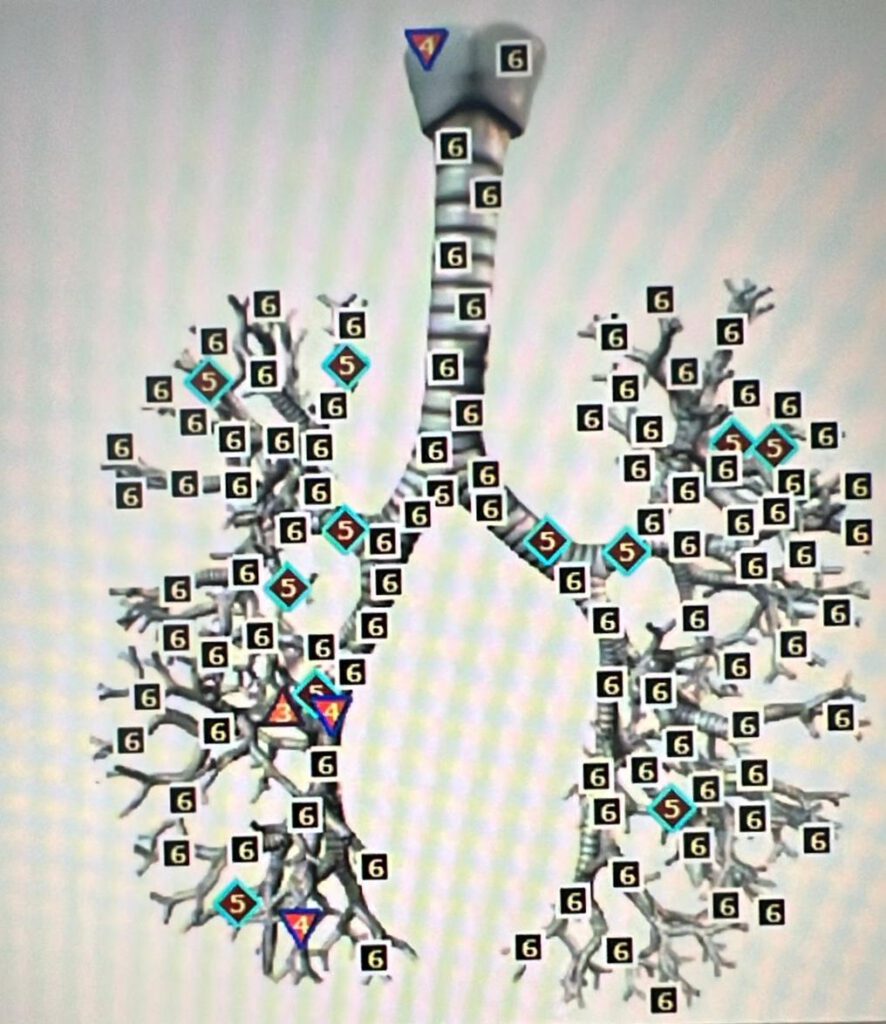

Rechts zie je zelfde afbeelding maar dan met de bacterie.

Je ziet dat de luchtpijp en bronchiën behoorlijk verzwakt worden door de bacteriën, want je ziet dus allemaal zessen en een aantal vijven en twee vieren en slechts 1 x een drie!